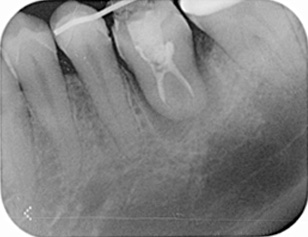

パノラマX線写真

デンタルX線写真う蝕(虫歯)も大きく、治療困難、抜歯が適応です。